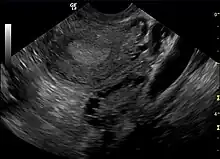

| A polycystic ovary shown on an ultrasound image. | |

The syndrome acquired its most widely used name due to the common sign on ultrasound examination of multiple (poly) ovarian cysts. These "cysts" are actually immature follicles not cysts. The follicles have developed from primordial follicles, but the development has stopped ("arrested") at an early antral stage due to the disturbed ovarian function. The follicles may be oriented along the ovarian periphery, appearing as a 'string of pearls' on ultrasound examination.

- Gynecologic ultrasonography, specifically looking for small ovarian follicles. These are believed to be the result of disturbed ovarian function with failed ovulation, reflected by the infrequent or absent menstruation that is typical of the condition. In a normal menstrual cycle, one egg is released from a dominant follicle – in essence, a cyst that bursts to release the egg. After ovulation, the follicle remnant is transformed into a progesterone-producing corpus luteum, which shrinks and disappears after approximately 12–14 days. In PCOS, there is a so-called "follicular arrest"; i.e., several follicles develop to a size of 5–7 mm, but not further. No single follicle reaches the preovulatory size (16 mm or more). According to the Rotterdam criteria, which are widely used for diagnosis,[10] 12 or more small follicles should be seen in an ovary on ultrasound examination.[58] More recent research suggests that there should be at least 25 follicles in an ovary to designate it as having polycystic ovarian morphology (PCOM) in women aged 18–35 years.[64] The follicles may be oriented in the periphery, giving the appearance of a 'string of pearls'.[65] If a high resolution transvaginal ultrasonography machine is not available, an ovarian volume of at least 10 ml is regarded as an acceptable definition of having polycystic ovarian morphology instead of follicle count.[64]